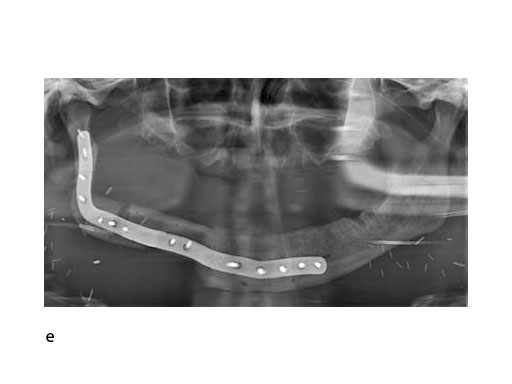

With the design of the bony framework being ready, the reconstruction plate is molded to the geometry of the outer surface of the neomandibular division. The plate profile (thickness 2.0 or 2.5 mm) is chosen and the plate screw hole pattern is customized. Relative to the osteotomy sites, the fibular segment configuration, and the adjacent native bone, the number, position, and angulation (up to 15) of the plate screw holes is specified with respect to overall stability. A defined screw hole position facilitates accessibility for screw insertion and avoids interference with nerves, tooth roots, osteotomy interfaces, and existing/future implants.

Note: In contrast to a milled plate, a succinct set of abrupt bends or edges in a massive reconstruction plate is hardly bendable by hand. The screw length is preselected and screw convergence or tip collision (eg, in the symphyseal area) is precluded.

To conclude, it can be noted that the substractive milling process for the manufacturing of patient specific plates for mandibular reconstruction eliminates the need for manual back and forth bending. This improves the fatigue strength and allows for a lower overall plate profile in comparison to standard reconstruction plates.

A key advantage of patient specific plates for the mandible is the transfer of the bone work design into surgery without any compromise by insufficiently adapted plates that could lead to unwanted displacement, and in the extreme, to healing problems. A decisive requirement is to establish a complete digital workflow for the design and production of all necessary tools and models, to finally obtain an optimally fitting bony reconstruction stabilized by a patient specific plate.